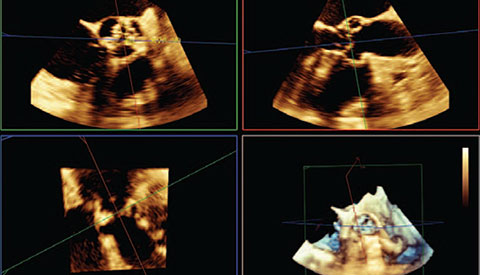

تم تشخيص أحد المرضى لديك بتضيّق في الصمام الأورطي المصحوب بأعراض. يبلغ عمر المريضة 85 عامًا وهي تعاني من السكري وارتفاع ضغط الدم. أنت تدرك خطورة وضعها الصحي ما يجعلها غير مناسبة لجراحة القلب ولكن يسمح لها بأن تكون مرشحة لاستبدال الصمام الأورطي باستخدام القسطرة (TAVR). في يومنا هذا، تمنح حلول التصوير المبتكرة والأجهزة التي تعمل عن طريق الجلد الأمل لبعض المرضى الذين لا تتوفر لهم حتى الآن أي خيارات علاجية أخرى.